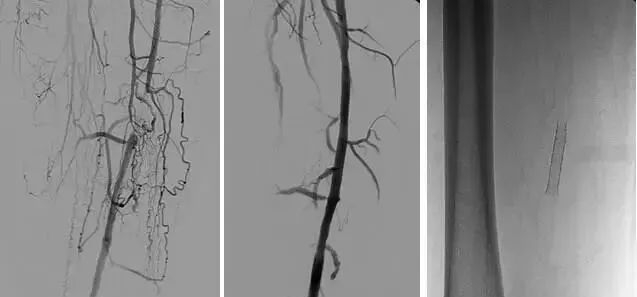

3、经皮腔内血管成形术(Percutaneous transluminal angioplasty,PTA)

60年*开代**始应用于动脉,使狭窄的血管扩张,70年代研制双腔气囊导管成功后,得到广泛应用,多用于髂、股、腘动脉及肾动脉。肾动脉PTA(或PTPA)多用于肾源性高血压,使狭窄肾动脉扩张,从而降低血压。PTA亦可用于冠状动脉,称为经皮腔内冠状动脉成形术(Percutaneous transluminal coronary angioplasty,PTCA),使硬化的冠状动扩张,以达到治疗冠心病的目的。PTA使用的导管为带胶囊的双腔导管,将胶囊段置于狭窄血管处,囊内注入含有造影剂的液体,加压至3~6个大气压,每次持续10—15o。加压可重复3~4次,多数能使狭窄血管达到扩张的效果。

PTA多用于动脉粥样硬化性狭窄的血管,其机理是粥样斑块受压,内膜和中层撕裂、伸展,使管腔增宽。其他原因的血管狭窄,如多发性大动脉炎,先天性血管狭窄,有时也可用PTA治疗。